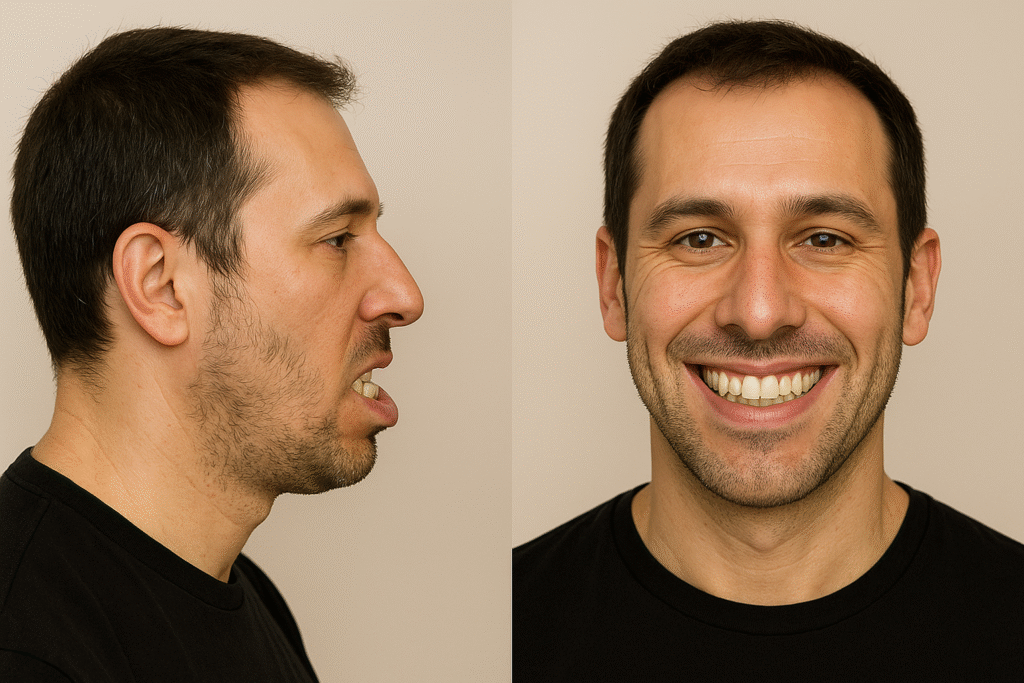

Corrective jaw surgery, also known as orthognathic surgery, is a specialized procedure designed to address irregularities in the jaw bones and realign the jaws and teeth to improve their function. This surgery can be recommended for individuals experiencing difficulties with chewing, speech, breathing, or facial symmetry due to skeletal misalignment. At Ibdaa Dental Clinic, our professional surgeons utilize advanced 3D imaging and precise digital planning to deliver personalized treatments that not only enhance your oral health, but also boost your confidence and facial aesthetics.